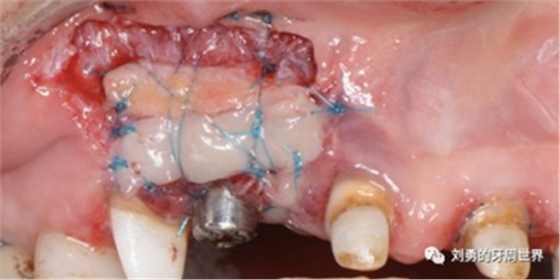

上圖中,種植體唇側(cè)缺乏附著齦,從上腭取瓣,常規(guī)做法:取長而寬的齦瓣,這樣供區(qū)面積大,術(shù)后疼痛重。

為了減少痛感,從雙側(cè)上腭取多條長而窄的齦瓣進(jìn)行移植,這樣每個供區(qū)的傷口都比較窄,可以減少術(shù)后的痛感。